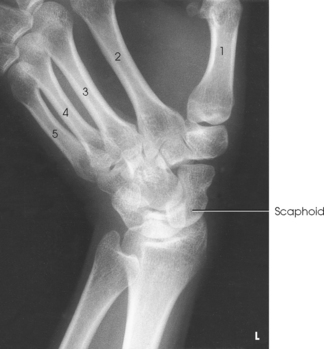

• Carpals: Bones of the wrist (Fig. 4-1)

Five metacarpals, which are cylindric in shape and slightly concave anteriorly, form the palm of the hand (see Fig. 4-1). They are long bones consisting of a body and two articular ends—the head distally and the base proximally. The area below the head is the neck where fractures often occur. The first metacarpal contains two small sesamoid bones on its palmar aspect below the neck (see Fig. 4-1). A single sesamoid is often seen at this same level on the second metacarpal. The metacarpal heads, commonly known as the knuckles, are visible on the dorsal hand in flexion. The metacarpals are also numbered 1 to 5, beginning from the lateral side of the hand.

The wrist has eight carpal bones, which are fitted closely together and arranged in two horizontal rows (see Fig. 4-1). The carpals are classified as short bones and are composed largely of cancellous tissue with an outer layer of compact bony tissue. These bones, with one exception, have two or three names; this atlas uses the preferred terms (see box). The proximal row of carpals, which is nearest the forearm, contains the scaphoid, lunate, triquetrum, and pisiform. The distal row includes the trapezium, trapezoid, capitate, and hamate.